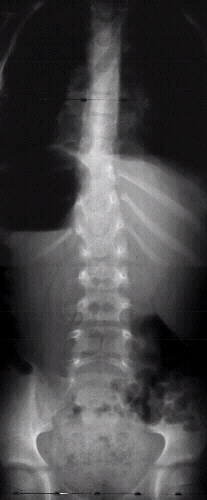

This 7 year old male presented to the cerebral palsy clinic with mild development delay, hyperactivity, and kyphosis. On physical examination he was slightly small for age (5th percentile weight for age, 10th percentile height for age) and had hyperactivity. He had no clonus or spasticity but a slightly clumsy gait.

Based on the x-ray a further evaluation should include a work up for osteogenesis imperfecta.

These changes on the spinal x-ray suggest a high probability of a malignant process.